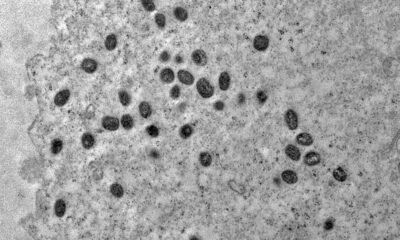

A Secretaria de Administração Penitenciária (Seap) confirmou, hoje (2), o primeiro caso do vírus da varíola dos macacos em uma unidade prisional do Rio de Janeiro....